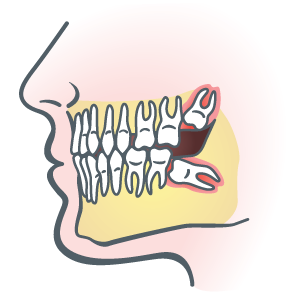

Baby Teeth and Teething

Being mammals, we sport two sets of teeth, the primaries and the permanent. Assuming Mom has already lent strength to her baby's teeth during pregnancy—beginning from week seven of prenatal life—teeth grow through two stages. In the first [...]